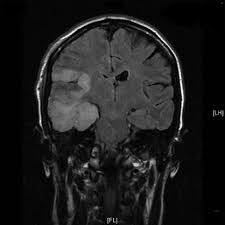

Herpes simplex (hsv) encephalitis is the most common cause of fatal sporadic fulminant necrotizing viral encephalitis and has characteristic imaging findings. Metabolic, vascular, neoplastic, infective and paraneoplastic diseases. A 40‑year‑old male patient with herpes simplex virus encephalitis presented with altered sensorium. Key imaging features include bilateral or unilateral signal abnormality in the temporal lobes that extends to the limbic system, early hemorrhagic changes, restriction on dwi, and abnormal enhancement. Mri revealed hyperintensities on t2 weighted images in both frontal and temporal lobes suggestive of herpes simplex encephalitis (fig 1).

A feasibility study of quantifying longitudinal brain changes in herpes simplex virus (hsv) encephalitis using magnetic resonance imaging (mri) and stereology. In the present study, flair bth was most frequently seen in patients with hsv encephalitis. Mri is the diagnostic modality of choice abnormal in 90%; Herpes simplex virus (hsv) encephalitis hsv encephalitis (hsve) is the most common cause of infectious encephalitis (1); The basal ganglia are usually spared. Encephalitis, magnetic resonance imaging, meningoencephalitis, viral. that appeared in a recent issue of clinical infectious diseases. Although far less common, essentially any part of the central nervous system can be involved 9. 1 mri t2 weighted image, showing bilateral temporal lobe hyperintensities. However, mimics of hse, including other infections and increasingly recognized autoimmune causes, have been described in cases of tl encephalitis. Two subtypes are recognized which differ in demographics, virus, and pattern of involvement. Because early diagnosis is possible in more cases of herpes simplex encephalitis (hse) as a result of the high sensitivity of mri, now widely available, a larger number of patients are receiving appropriate treatment with iv acyclovir. Limbic encephalitis, mca ischaemia, tumours, effects of seizures) hyperintense t2 signal in the medial temporal lobes, inferior frontal lobes and insula basal ganglia are usually spared